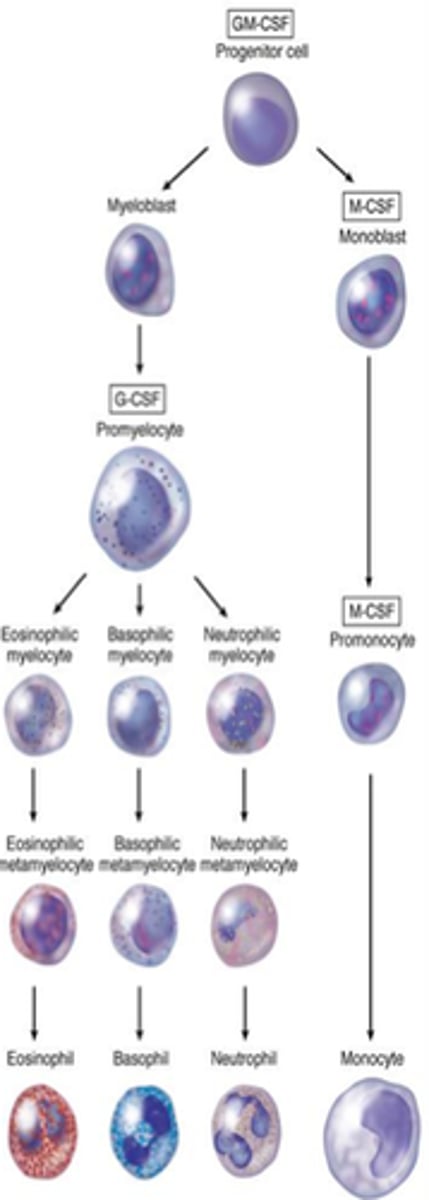

GM-CSF

Granulocyte-macrophage colony-stimulating factor; stimulates granulocytes and monocytes

Granular leukocytes

Neutrophils, eosinophils, basophils

Agranular leukocytes

Lymphocytes and monocytes

Neutrophils

Structure: Nuclei has three or more lobes, granules stain light pink

Function: The most common WBC; fights bacterial infections by engulfing bacteria by phagocytosis

Eosiniphils

Structure: Nuclei has two lobes, granules stain bright red

Function: A WBC that digests and destroys parasitic worms, they also play a role in allergy and immune response

Basophils

Structure: Nuclei is U or S shaped but is obstructed by HUGE blue granules

Function: A WBC that produces histamine --> causing inflammation during an immune response

Monocytes

Structure: Largest WBCs, U shaped nucleus

Function: A large WBC that transform into macrophages to fight off viruses and chronic infections